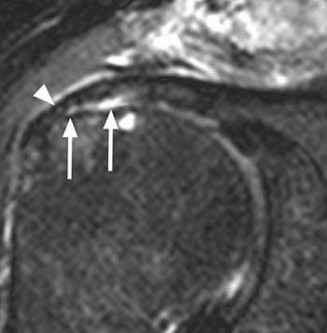

A 24-year-old, male athlete sustains an anterior shoulder dislocation. His MRI is shown in Figure 2–32 . Figu…